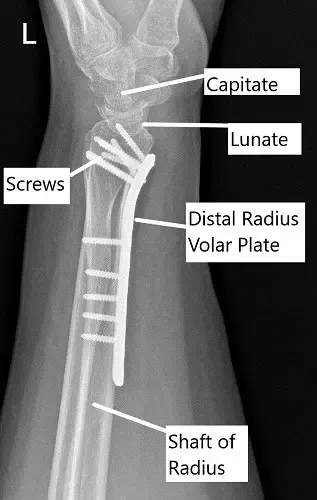

Post-operative x-ray of the wrist in lateral view.

A 5-hole distal radius plate was put and held with a radial olive wire. AP and lateral views were checked and found to be satisfactory. Provisional fixation of the plate was done with a cortical screw oblong hole. Fixation of the plate to the proximal radius was done with a nonlocking screw. Again, checking the reduction to be acceptable, the distal plate was fixed to the distal end of the radius.

A 26 mm cortical nonlocking screw was used to pull the plate to the bone. This screw was later removed and exchanged for a locking screw. The distal fixation was done using multiple locking screws. A proximal fixation of the radius was done using a combination of locking and non-locking screws. The final fixation was checked under C-arm and found to be acceptable.